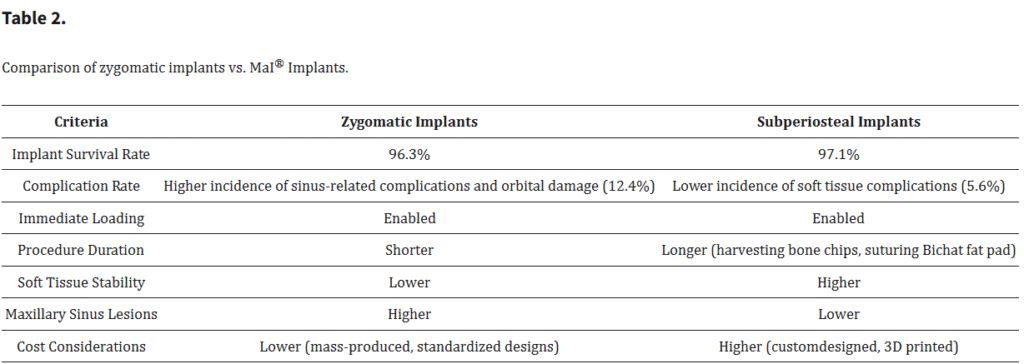

骨膜下インプラントとザイゴマインプラントの比較にあたり、いくつかの基準が考慮された(Table 2)。

3.1. インプラントの失敗

重度の上顎萎縮症例において、個別設計のインプラントはザイゴマインプラントと比較して低い失敗率を示した(Figure 8)。ザイゴマインプラントの生存率(96.3%)と骨膜下インプラントの生存率(97.1%)との間に統計学的に有意な差は認められなかったものの(p = 0.278)、骨膜下インプラントのわずかに高い生存率は、その患者固有の解剖学的形態に適合するカスタマイズ設計によるものと考えられる。この個別化アプローチにより、インプラントおよび周囲骨への応力集中が軽減され、安定性および長期的な統合が向上した(Figure 9)。

3.2. 手術時間

ザイゴマインプラントの埋入はより短時間で行うことができたが、個別設計インプラントの精緻な埋入は高い精度と安定性を確保し、手術時間がやや長くなる一方で長期的な合併症を減少させる結果となった。ザイゴマインプラントはテンプレートを用いずフリーハンドで埋入されたのに対し、一部の個別インプラントはテンプレートを用いてガイド下に埋入された。個別インプラントにおいて手術時間が長くなったのは、骨をテンプレートに適合させるための調整が必要であったためである。さらに、骨膜下インプラントでは下顎外斜線(linea obliqua)からの骨移植が併用された症例もあり、これによっても手術時間が延長した(Figure 10)。

3.3. 上顎洞の術後病変

個別設計インプラントを使用した患者は、ザイゴマインプラントを使用した患者と比較して、術後の上顎洞病変の発生が少なかった(p < 0.05)。個別インプラントの設計と埋入手技により、上顎洞粘膜の穿孔やそれに関連する合併症のリスクが最小限に抑えられた(Figure 11)。

3.4. 軟組織退縮

個別設計インプラントでは、ザイゴマインプラントと比較して軟組織退縮の発生頻度が有意に低かった(p < 0.05)。個別インプラントの精密な設計と埋入位置により、軟組織の統合が向上し、審美的な結果も改善された(Figure 12)。

3.5. 術後粘膜の厚さ

術後の粘膜厚は、個別設計インプラントを使用した患者でより安定していた。個別インプラントに伴う周囲構造への機械的ストレスの軽減が、術後成績の改善に寄与したと考えられる(p < 0.05)(Figure 13)。

3.6. 炎症およびインプラントの動揺

個別設計インプラントを使用した患者では、ザイゴマインプラントと比較して炎症およびインプラントの動揺が著しく低かった。個別インプラントの高い安定性と生体適合性が、これらの合併症の軽減に寄与したと考えられる(p < 0.05)(Figure 14)。